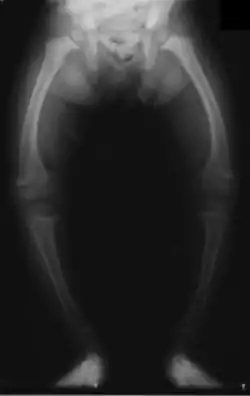

![]() Røntgenbillede af en to-årig med engelsk syge; de bøjede knogler i benene skyldes nedsat deponering af mineraler i knoglemassen. | |

Hos børn med engelsk syge forbliver knoglerne bløde og bøjelige. D-vitaminets helbredende virkning på engelsk syge blev opdaget i 1918.